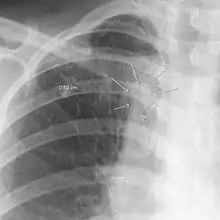

The arrows denote an ill-defined nodular opacity in medial aspect of right upper lobe with ill-defined rim of lucency surrounding it | |

In radiology, the air crescent sign is a finding on chest radiograph and computed tomography that is crescenteric and radiolucent, due to a lung cavity that is filled with air and has a round radiopaque mass.[1] Classically, it is due to an aspergilloma, a form of aspergillosis, that occurs when the fungus Aspergillus grows in a cavity in the lung.[2] It is also referred as Monad sign.[3]